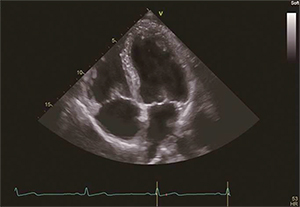

Vivid S60

Vivid S60による診断画像